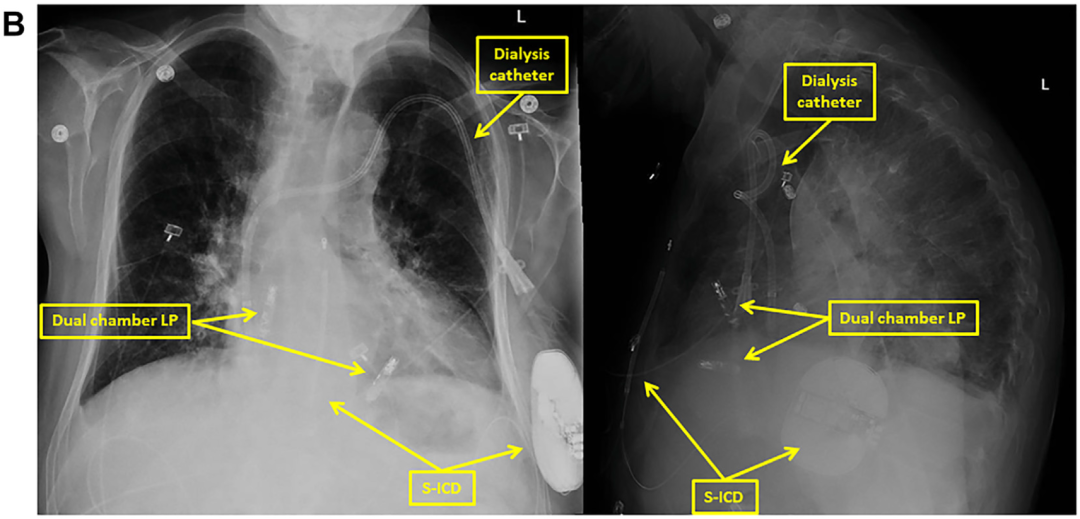

但后通过手动筛查工具评估,发现Primary向量和Secondary向量均显示出合理的电图形态,因此,最终将S-ICD植入(图B);

图B 植入后S-ICD与AVEIR DR透视影像图

术中,Primary、Secondary向量均显示QRS感知良好,无T波过感知现象;使用Secondary向量成功诱发并终止心室颤动,一次65焦耳电击即成功复律。

此例为首例AVEIR DR双腔无导线起搏器与S-ICD联合应用病例报道,治疗过程顺利,结果满意;同时,术中对于S-ICD进行了诱颤测试,65焦耳电击并未对AVEIR DR造成影响;